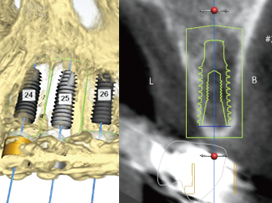

• CT를 이용한 3D 진단

CT 촬영한 3차원 데이터와 구강 모형을 통해 뼈, 잇몸, 신경을 통합적으로 고려하여 정밀 진단합니다.

• 컴퓨터로 수술 계획 수립

컴퓨터로 모의 수술을 통해 수술 위치를 설정하고, 그대로 수술될 수 있도록 맞춤형 가이드를 제작합니다.